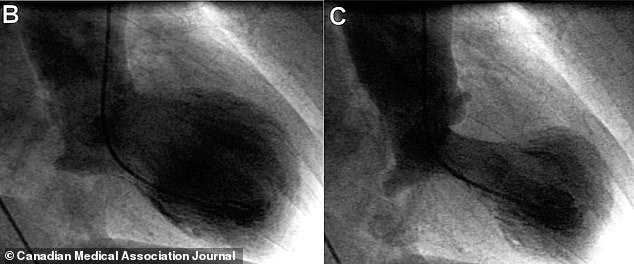

Um ECG usa ondas sonoras para capturar uma imagem do coração e determinar se o compartimento inferior tem uma forma distintiva. Na síndrome do coração partido, o principal compartimento de bombeamento do coração incha na parte inferior enquanto o pescoço permanece estreito.

Um exame de sangue também verifica níveis elevados de uma proteína chamada troponina, que entra na corrente sanguínea quando o músculo do coração é danificado. Mas a única maneira de descartar com certeza um infarto envolve um procedimento chamado cateterismo cardíaco.

Um tubo fino é introduzido em uma artéria e levado até o coração, onde um contraste é injetado para criar um raio-X detalhado das artérias coronárias.

Se eles estiverem livres de obstruções, os médicos podem afirmar com confiança que o paciente não está tendo um infarto do miocárdio e, em vez disso, provavelmente está experimentando a cardiomiopatia takotsubo.